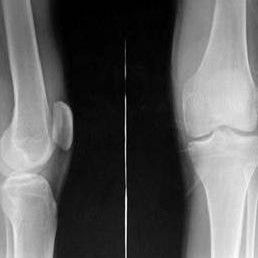

好發年齡為20—40歲。以膝關節最多見,膝關節可觸及柔韌腫塊,並有瀰漫性壓痛,甚至可侵蝕骨組織,腱鞘也可發生,手的屈肌腱鞘比較多見,形成孤立性硬韌結節,關節積液可抽出血性和黃褐色關節液。

絨毛結節性滑膜炎膝關節受累時髕上囊及髕骨腫脹明顯,積液多的俘髕試驗陽性。增生的滑膜組織有時可穿破後關節囊而進入膕窩,並沿小腿後方肌間隙向下蔓延,產生深在的瀰漫性腫脹。踝關節受累者腫脹在內、外踝周圍最明顯。髖關節受累時腫脹多位於髖關節前方。

不論為瀰漫性或局限性,患肢都有輕度的肌肉萎縮。關節穿刺可抽出血性或咖啡色液體,這種關節液很特殊,具有診斷價值。